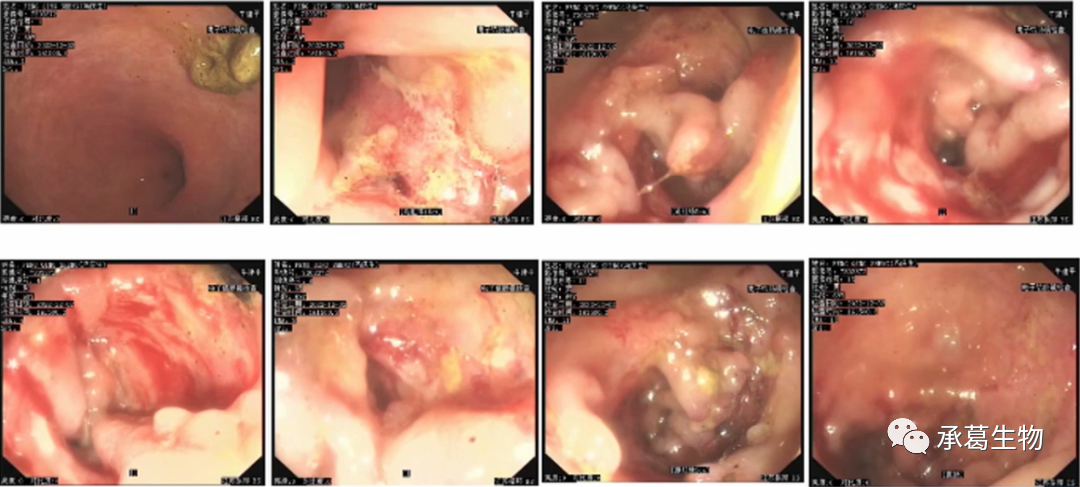

行菌群移植(液體活菌腸溶膠囊)治療艱難梭菌感染,40粒/日,連續(xù)3天,移植穩(wěn)定后擬行英夫利昔單抗治療。菌群移植10天后因肺部感染癥狀加重予抗感染治療。2022年11月15日復(fù)查腸鏡示表面糜爛、息肉樣增生,散在片狀糜爛內(nèi)鏡無法通過,病理示管狀腺瘤。

(2022年11月15日腸鏡)

繼續(xù)予營養(yǎng)支持及調(diào)節(jié)腸道菌群治療。大便次數(shù)較前減少4-5次/日,黃色糊狀便。2022年11月22日再次復(fù)查腸鏡,回腸末端未見明顯異常,全結(jié)腸散在潰瘍糜爛,較前未見明顯改善。

予第二次菌群移植,考慮患者腸腔狹窄,移植方案調(diào)整為20/日,連續(xù)6日移植。移植后大便次數(shù)增加至10/日,水樣便,未經(jīng)處理后自行減少至4-5/日,稀糊樣便。